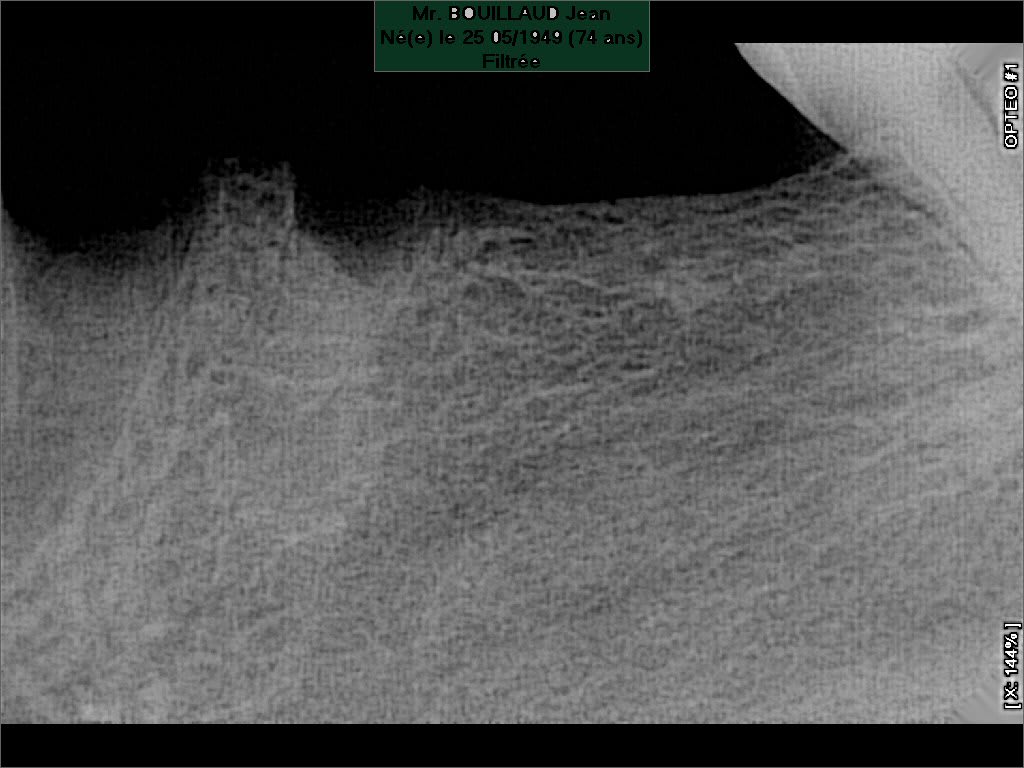

Galiléo

31/08/2023 à 14h10

merci pour la photo!!